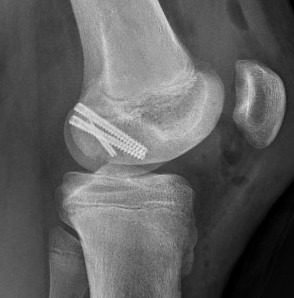

1.  AP screws

Hoffa Fracture ORIF APHoffa Fracture Lateral

2.  PA screws

Hoffa Fracture ORIF PA screws